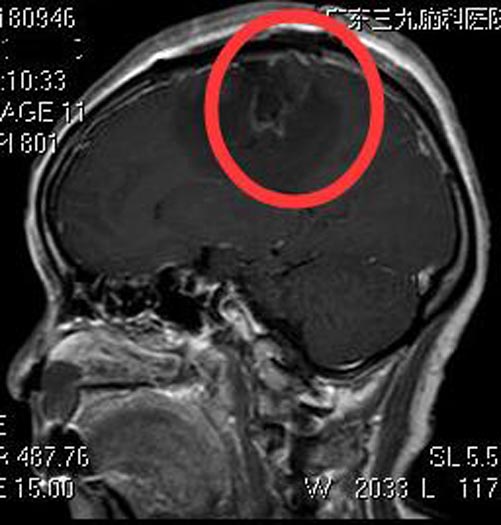

三天前,莲姨发热、头痛、头晕,再次出现左侧肢体抽搐,并左侧肢体乏力,不能行走。当地医院头颅CT检查提示:右侧额顶部占位,考虑肿瘤性病变,建议上级医院进一步治疗。广东三九脑科医院头颅MR检查提示:右侧额顶部中央浅表区镰旁占位性病变,大小约为4.5cm×5.2cm×4.2cm,考虑脑膜瘤。

综合神经外科鲁明主任主刀,在全麻下行右侧额顶部镰窦旁脑膜瘤切除术,显微镜下见右侧额顶灰白色肿瘤组织,质中,与脑膜及大脑镰粘连紧密,部分肿瘤侵犯上矢状窦,镜下将肿瘤全切除,手术经过顺利。术后没有了抽搐,莲姨回家的第一件事就是继续她的广场舞。术后病理结果提示:脑膜瘤,WHO I级。